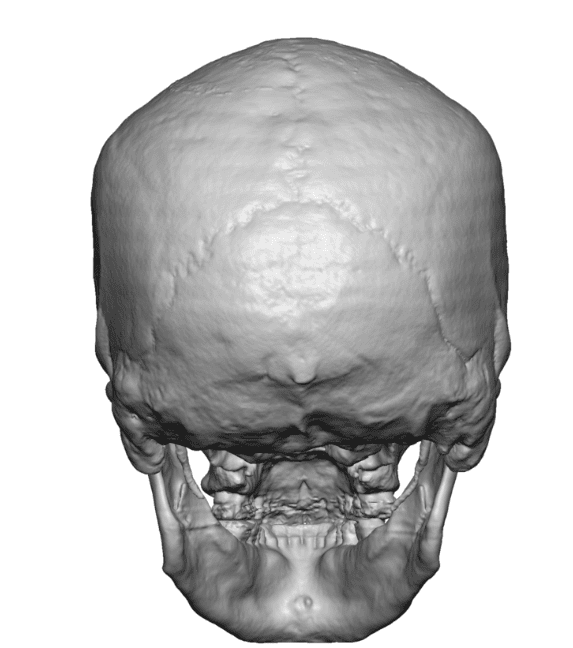

Desire for a higher and more prominent crown of the skull.

Crown of skull augmentation using a custom skull implant.

Desire for a higher and more prominent crown of the skull.

Crown of skull augmentation using a custom skull implant.